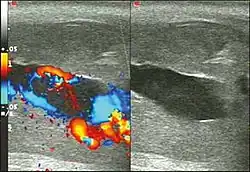

Priapizm typu wysokoprzepływowego powstaje zwykle w następstwie urazu okolicy krocza, rzadziej jest idiopatyczny, a całkiem wyjątkowo występuje w przebiegu anemii sierpowatokrwinkowej.

Jeżeli przyczyną jest uszkodzenie tętnicy głębokiej prącia, z wytworzeniem przetoki tętniczo-jamistej to polecanym sposobem leczenia jest zastosowanie wybiórczej embolizacji uszkodzonej tętnicy.